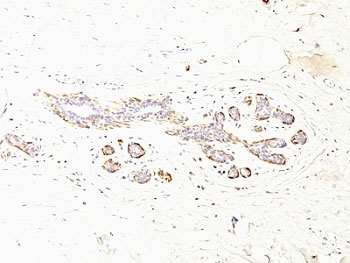

IHC: Formalin-fixed, paraffin-embedded human breast carcinoma stained with SMMHC antibody (MYH11/923).